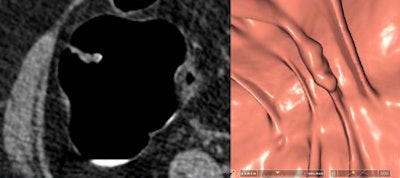

![]() |

| Two true-positive lesions detected by CAD were dismissed by radiologists due to low conspicuity and a "cigarlike" appearance; both were also detected at conventional colonoscopy. |

"Six lesions located on the haustral folds showed a much higher conspicuity on the 3D endoluminal views than on 2D," he said. For polyps on folds, focal thickening and surface nodularity were key features leading to their detection.

| Six lesions detected at CAD and VC on haustral folds were more conspicuous in 3D endoluminal views (right) than on 2D (left) visualization. Key features included focal fold thickening and surface nodularity. |